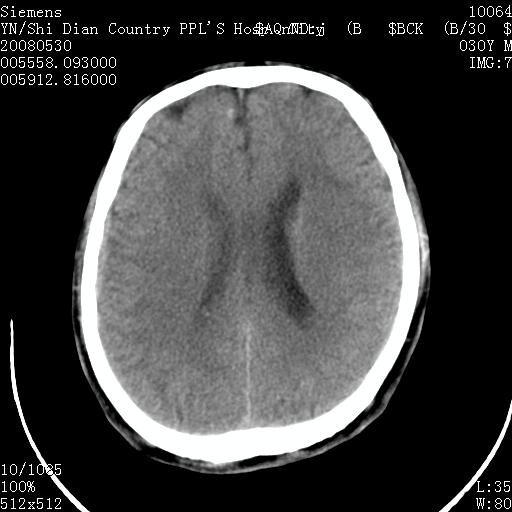

以下是引用随光逐影在2008-7-10 15:19:00的发言:[br]1)考虑左侧尾状核钙化。2)透间隔间腔与vergae腔并存。

以下是引用卜一在2008-7-10 16:43:00的发言:[br]1)考虑左侧尾状核钙化。2)透间隔间腔形成。支持!